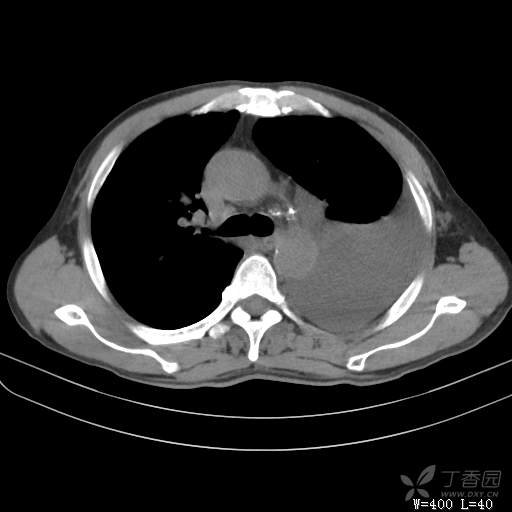

简要病史:胸闷、憋气伴低热1月

体格检查:T:37.6℃;P:92次/分;R:20次/分;Bp:100/60mmHg,神清,呼吸平稳,周身未触及肿大淋巴结,右肺及左上肺叩诊清音,左下肺叩诊浊音,右肺及左上肺呼吸音粗,左下肺未闻及呼吸音,心率92次/分,律齐,无杂音。腹部平坦,软,全腹无压痛,无反跳痛及肌紧张,肝脾肋下未触及,双下肢无水肿。

辅助检查:白细胞数目4.41 × 10^9/L,中性粒细胞百分比82.1%,*血红蛋白111g/L,*血小板数目91 × 10^9/L,凝血四项:凝血酶原时间12.5秒,国际标准化比值1.07,活化部分凝血酶原时间36.1秒,纤维蛋白原浓度6.52g/L,肾功能示:肌酐47.4umol/L,尿酸150umol/L,电解质示:钠133.5mmol/L,D-二聚体0.88mg/L,血沉67.71MM/H,C-反应蛋白114.6mg/L,肝功能:*总蛋白49.6g/L,*白蛋白27.4g/L,查胸水常规及胸水生化提示渗出液,胸水ADA154U/L,查胸水病理未见肿瘤细胞。超声:腹膜后有3~4枚肿大淋巴结,直径1~1.5厘米,余浅表淋巴结不大。

临床诊断:左侧胸腔积液

治疗经过:胸水引流。胸水白蛋白23.8克/升,乳酸脱氢酶275单位/升,胸苷激酶182单位/升,胸水外观黄色混浊,总细胞4320个/微升,白细胞4320个/微升,单核细胞80%,多核细胞20%。考虑结核性胸膜炎,结果查肿瘤标志物、胸水细胞学阴性,胸水TB—DNA阴性,结核菌素试验+,结核抗体阴性,TB-SPOT阴性,胸膜活检阴性。怎么办?